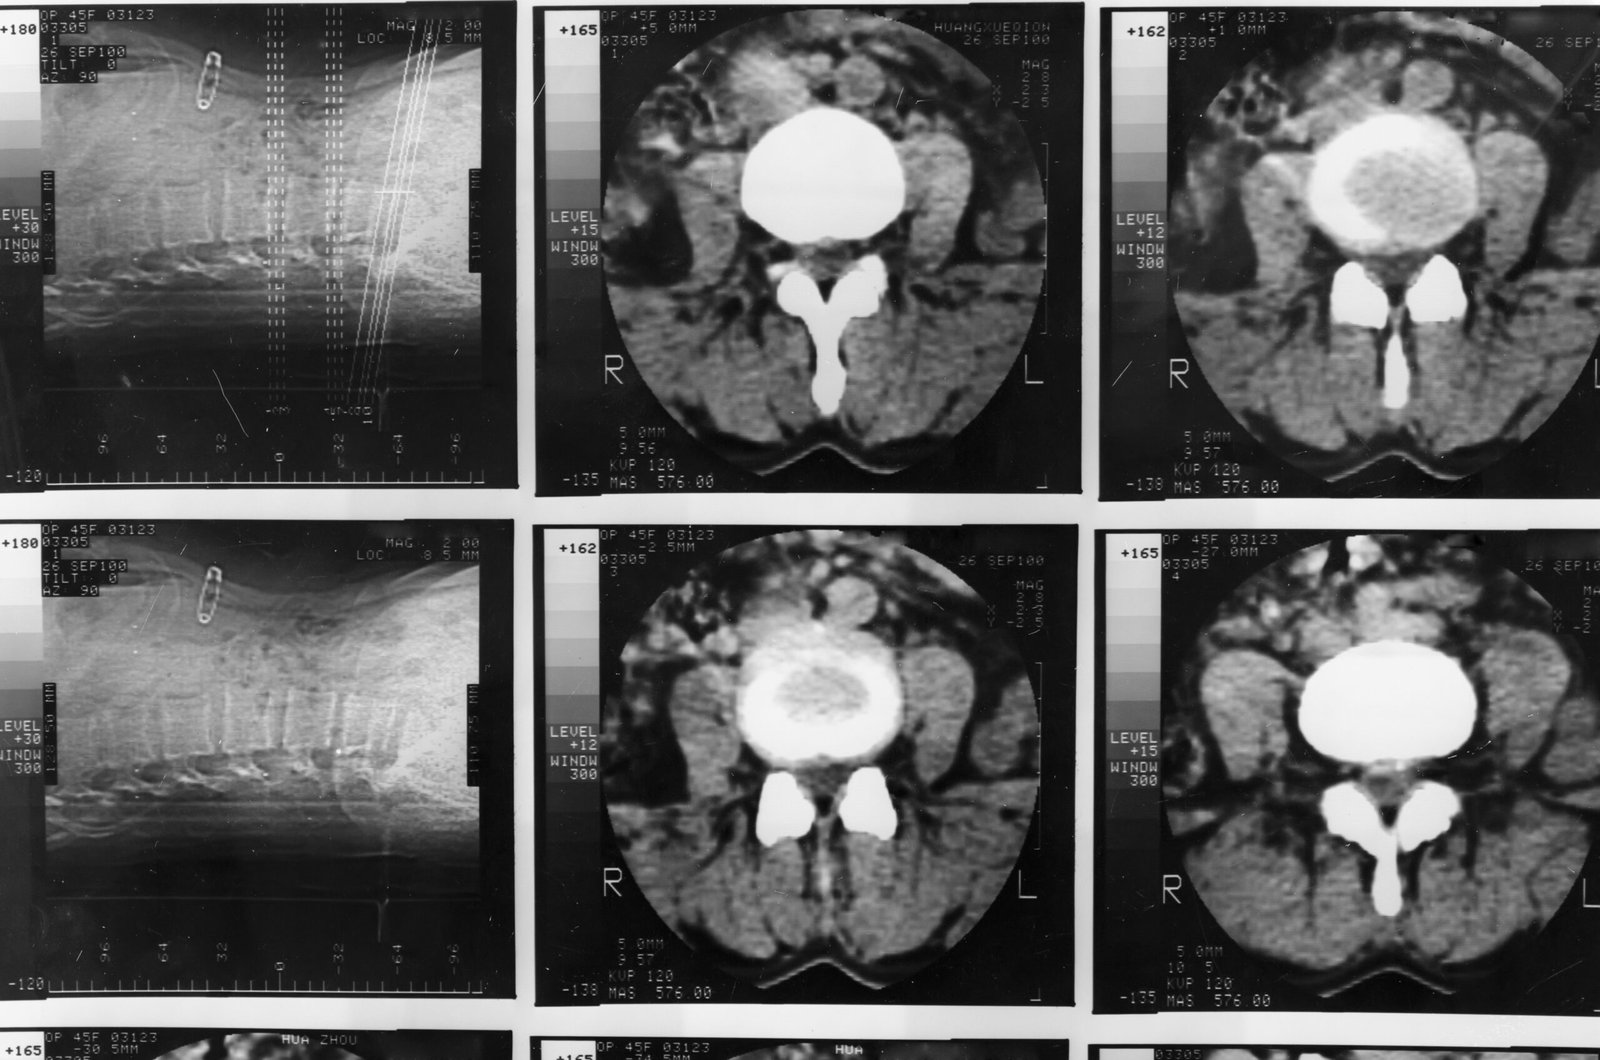

2. Imaging and Scans

Advanced imaging techniques help identify where it has spread and how extensive it is. These scans provide critical information for treatment planning. Common imaging tests include:

- CT scans

- MRI scans

- PET scans

- Bone scans

Each test offers different insights into its behaviour and spread.